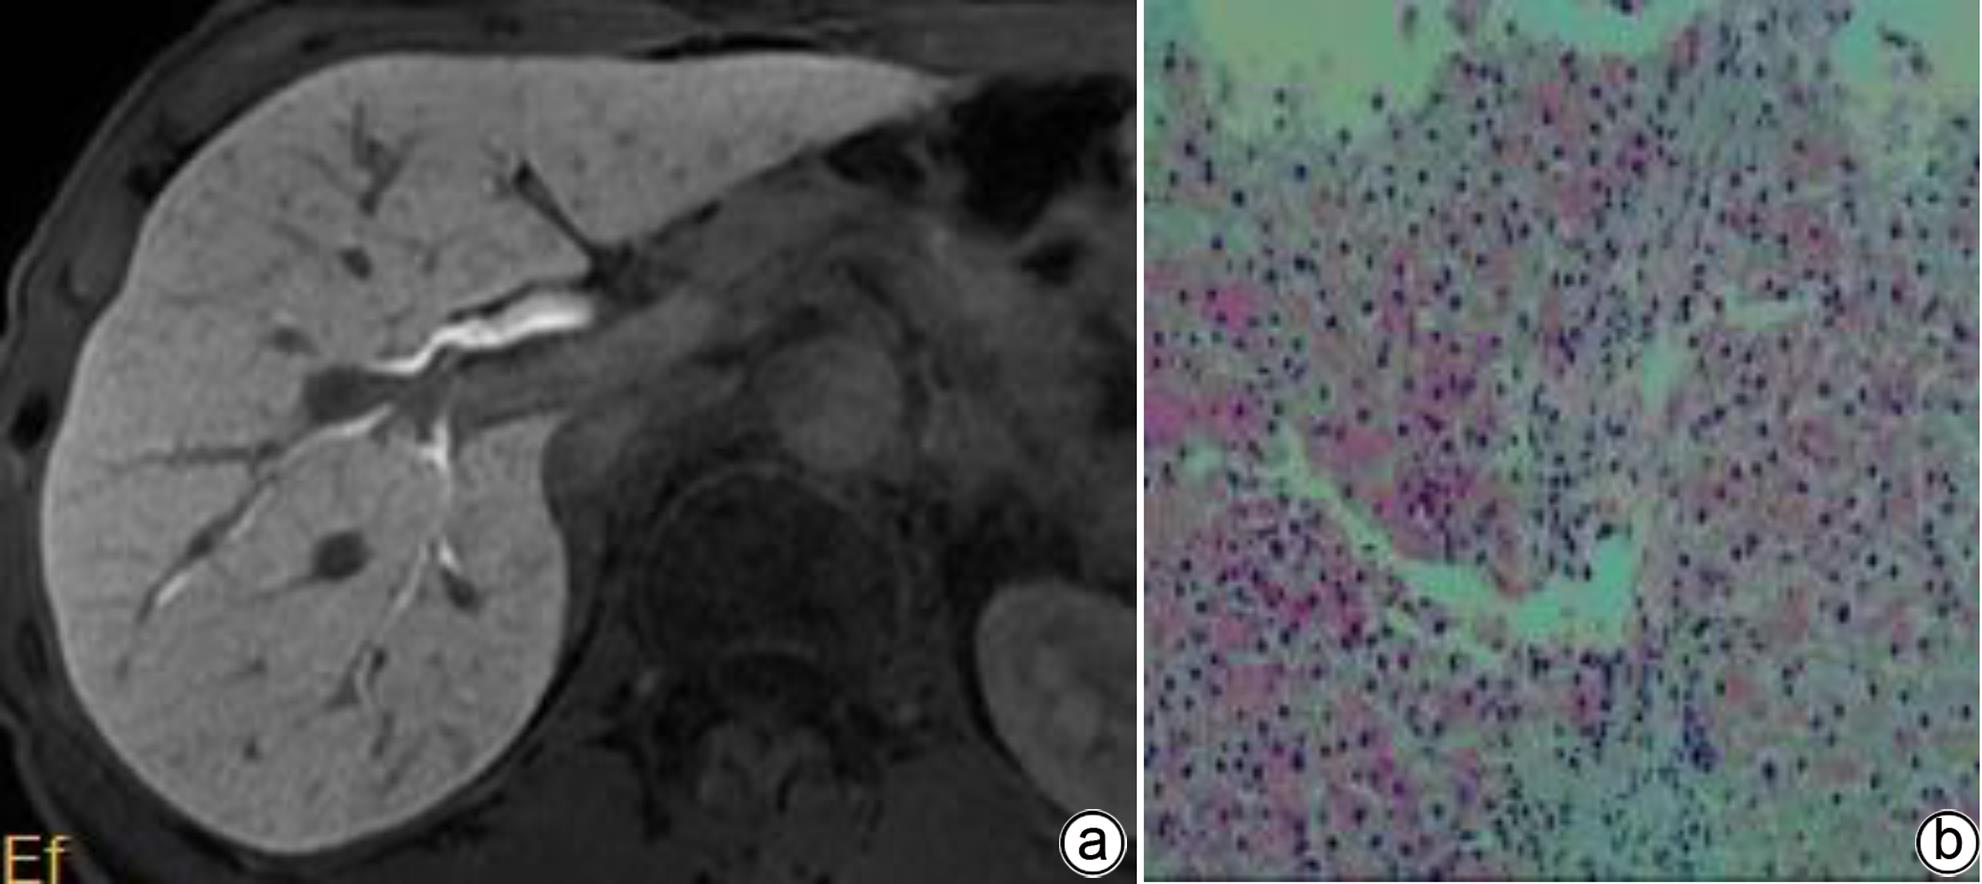

Value of MRI biliary score and liver/muscle ratio in evaluating the pathological grade of liver fibrosis

Lu HUANG, Lijian LU

2024, 40(4): 720-725. DOI: 10.12449/JCH240413

Abstract(1187) HTML (328) PDF (1168KB)(71)

Abstract:

Objective  To investigate the value of biliary score and hepatic signal intensity-to-muscle signal intensity ratio (HMR) obtained by multiphase contrast-enhanced MRI scan using Gd-EOB-DTPA in evaluating the pathological grade of liver fibrosis.  Methods  A retrospective analysis was performed for the MRI and clinical data of 51 patients with chronic hepatitis B liver fibrosis in Wuming Hospital Affiliated to Guangxi Medical University from January 2020 to May 2023. The 51 patients with liver fibrosis were divided into low-grade group (S1-S2) and high-grade group (S3-S4). GE Architact 3.0T MR scanner was used to perform MRI scans, including routine plain scan and contrast-enhanced scan at arterial phase, portal venous phase, delayed phase, hepatobiliary phase, and excretory phase, and biliary score and HMR were measured for the patients with different grades of liver fibrosis. The t-test was used for comparison of continuous data between groups, and the chi-square test or the Fisher’s exact test was used for comparison of categorical data between groups. The receiver operating characteristic (ROC) curve was plotted to evaluate the value of MRI indicators in determining the pathological grade of liver fibrosis.  Results  Among the 51 patients with liver fibrosis, there were 30 patients in the low-grade group and 21 in the high-grade group. Compared with the high-grade group, the low-grade group had significantly higher biliary score (3.67±0.55 vs 2.57±0.75, t=6.05, P<0.001) and HMR at portal venous phase (2.38±0.76 vs 1.97±0.18, t=2.41, P=0.020), delayed phase (2.48±0.70 vs 1.99±0.27, t=3.09, P=0.003), and hepatobiliary phase (4.10±0.63 vs 3.16±0.47, t=5.81, P<0.001). The above indicators had an area under the ROC curve (AUC) of 0.86, 0.79, 0.82, and 0.88, respectively, in distinguishing low- and high-grade liver fibrosis, with a positive rate of 70%, 63.3%, 83.3%, and 96.7%, respectively, and a negative rate of 90%, 95.2%, 74.1%, and 100%, respectively, in the diagnosis of high-grade liver fibrosis. Biliary score combined HMR had an AUC of 0.95, with a positive rate of 85.7% and a negative rate of 96.7%.  Conclusion  Biliary score and HMR at hepatobiliary phase obtained by multiphase contrast-enhanced MRI scan using Gd-EOB-DTPA has a relatively high diagnostic efficacy in distinguishing between low- and high-grade liver fibrosis and a certain guiding value for the diagnosis and treatment of liver fibrosis in clinical practice.